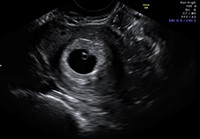

Ultrazvočne preiskave so ključnega pomena za spremljanje zdravja matere in ploda ter zagotavljanje varnejše nosečnosti. Preiskave izvajamo prek trebuha ali skozi nožnico, odvisno od stopnje nosečnosti in položaja ploda.